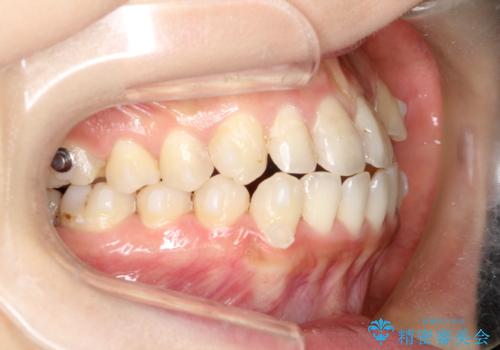

八重歯をインビザラインで非抜歯矯正

- 八重歯を主訴に来院されました。

インビザラインにて奥歯を後方に移動して八重歯が入るスペースを確保してく矯正する計画としました。

八重歯と前歯のガタガタがなくなり、歯並びがきれいになったのと、かみ合わせも改善することができました。